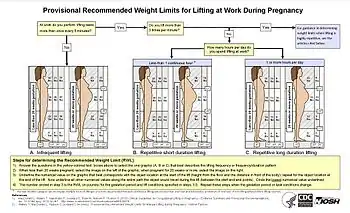

- ↑ Waters TR, MacDonald LA, Hudock SD, Goddard DE (February 2014). "Provisional recommended weight limits for manual lifting during pregnancy". Human Factors. 56 (1): 203–214. doi:10.1177/0018720813502223. PMC 4606868. PMID 24669554. Archived from the original on 1 April 2017.

- ↑ MacDonald, Leslie A.; Waters, Thomas R.; Napolitano, Peter G.; Goddard, Donald E.; Ryan, Margaret A.; Nielsen, Peter; Hudock, Stephen D. (2013). "Clinical guidelines for occupational lifting in pregnancy: evidence summary and provisional recommendations". American Journal of Obstetrics and Gynecology. 209 (2): 80–88. doi:10.1016/j.ajog.2013.02.047. ISSN 0002-9378. PMC 4552317. PMID 23467051.